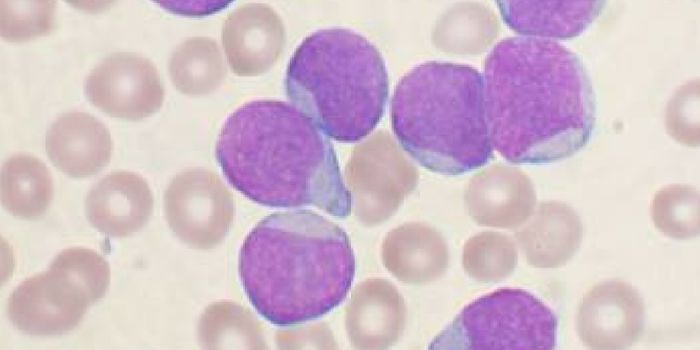

AUG 22, 2014Genetics & GenomicsEpigenetics has a large say in blood formation.

Blood stem cells have the potential to turn into any type of ... -

AUG 31, 2017CancerFor patients battling leukemia, there is hope in the form of a newly approved gene therapy. Called Kymriah, this is the ...